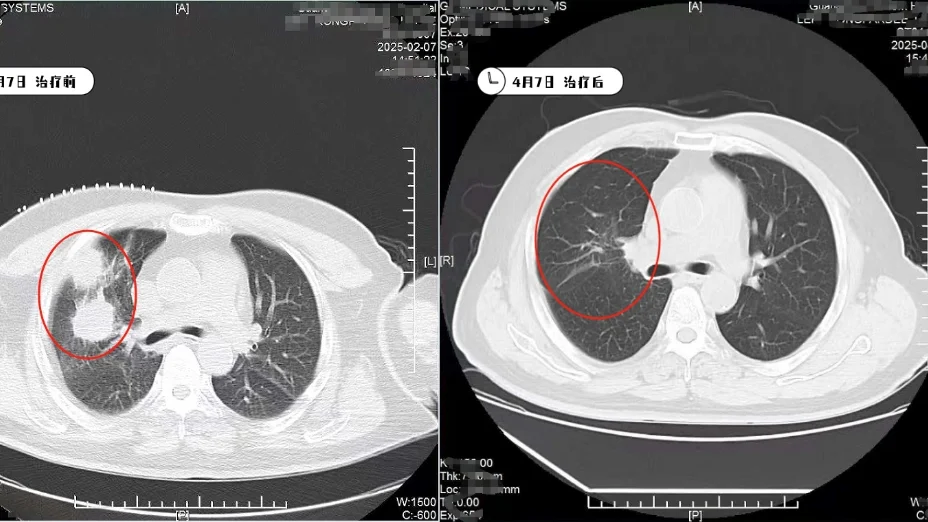

เมื่อฉันมาถึงโรงพยาบาลมะเร็งสมัยใหม่กว่างโจว มะเร็งปอดของฉันได้ลุกลามไปยังซี่โครง และการทำงานของไตใกล้ล้มเหลว แพทย์ไม่ได้ทำเคมีบำบัดต่อไปอย่างรุนแรง แต่ช่วยปรับสภาพร่างกายให้คงที่ก่อน ในเดือนกุมภาพันธ์ 2025 ฉันได้รับการทำ Kangbo Knife Cryoablation (การทำลายเนื้องอกด้วยความเย็น) ซึ่งแทบไม่เจ็บ หลังการรักษาหนึ่งวันฉันก็สามารถลุกจากเตียงได้ หลังจากนั้นได้รับการรักษาร่วมกับ Vidici-therapy ทำให้ขนาดเนื้องอกลดลงอย่างเห็นได้ชัดประมาณ 90%

จากที่แทบหมดลมหายใจ จนสามารถขับรถพาภรรยาไปเที่ยวได้ ผมรู้สึกอย่างแท้จริงว่า การมาที่ประเทศจีน เป็นการเลือกที่ให้ผมมีชีวิตใหม่